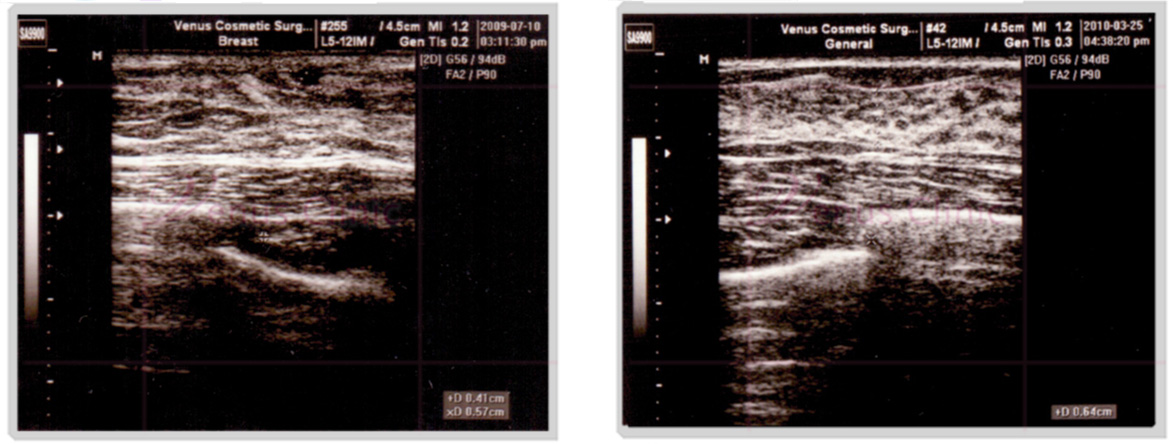

아랫사진의 왼쪽은 지방으로 이루어진 가성 여성형 유방의 초음파 사진이며, 오른쪽은 유선조직이 지방층 사이에 있는 진성 여성형 유방의 초음파 사진 입니다.

여유증 초음파 사진